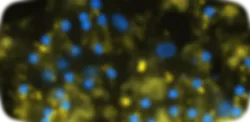

Steatosis

Lipid Droplet Accumulation

Hoechst (Nuclei) LipTOX (Neutral Lipids)

ER Stress

BIP/GRP78 Expression

Hoechst (Nuclei) BIP/GRP78 (ER Stress)